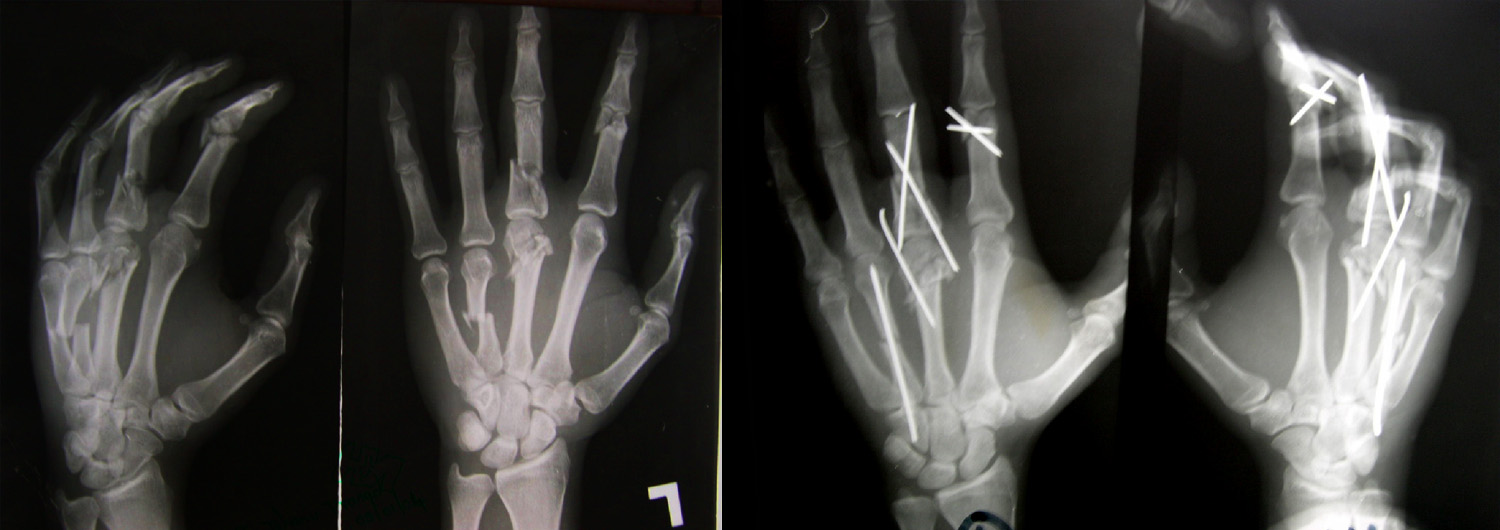

Fractures - Hand Conditions

Fractures, to both hand and wrist, are caused by an impact to the bone that is strong enough to break it. Symptoms include severe pain, loss of movement and swelling. Whatever caused the fracture – whether it was a fall, a fight, a sporting accident or anything else – can influence the treatment, so it"s helpful for the surgeon to know exactly how the break occurred. The problem will most likely be dealt with first by an Accident & Emergency department, before being passed on to a hand surgery team, including the surgeon, nurses and therapists.

A surgeon will take x-rays and physically examine the fracture before deciding on the best course of action. In some cases, the fracture may be treated with a splint, hand exercises and painkillers, but more serious breaks may require an operation. Following surgery, it"s likely the fracture will be placed in a splint or plaster, and rehabilitation will be overseen by therapists, who will advise on exercises to help future movement in the affected area.